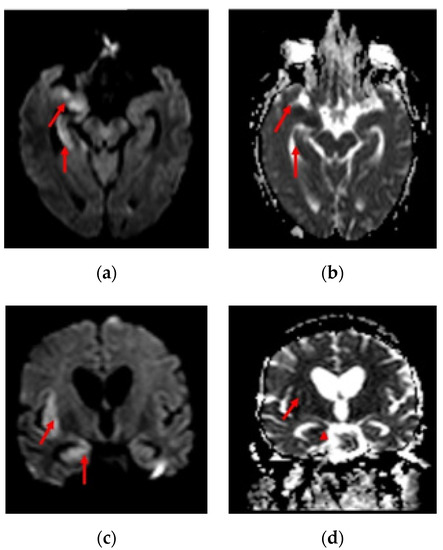

Overall, vascular pathology seen in imaging was significantly associated with fatality. A retrospective study by Benussi et al. also concluded that COVID-19 in patients with the cerebrovascular disease had significantly higher mortality than in-patients without COVID-19 [34]. The inflammatory pathology was significantly associated with the severity of the disease (refer Table 4 and Table 5). Severe COVID-19 patients may have developed neurological inflammation due to an intense inflammatory response or immunological phenomenon [13,35,36]. We present the MRI sections of two COVID-19 patients, one with multifocal ischemic stroke and another with encephalitis in Figure 2 and Figure 3, respectively.

Figure 3. 54-year-old man with COVID-19 RT-PCR positive and history of fever, cough for 7 days with recent onset headache and vomiting. MRI DWI (a) and ADC (b) showed diffusion restriction with corresponding hypointensity on ADC (red arrow) in the medial aspect of right anterior temporal lobe, hippocampus and sylvian cortex. MRI DWI (c) and ADC (d) showed diffusion restriction with corresponding hypointensity on ADC (red arrow) in the medial aspect of right anterior temporal lobe, hippocampus and sylvian cortex.